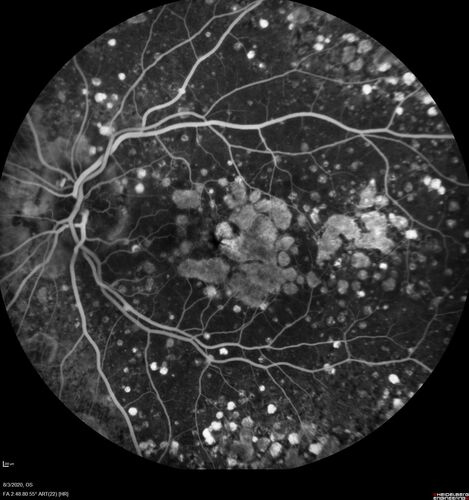

Dry AMD geographic atrophy and cystoid macular edema

79 year old vision is in for a checkup with no visual complaints in the left eye.  This is her better eye.  VA 20/200 OD, 20/50 OS.  3 years ago she had a CRVO in the left eye.  She is also diabetic for 20 years, has carotid insufficiency and anemia.  Left eye shows CME.  This was not treated and the vision improved to 20/40 over the next year although mild edema persisted.